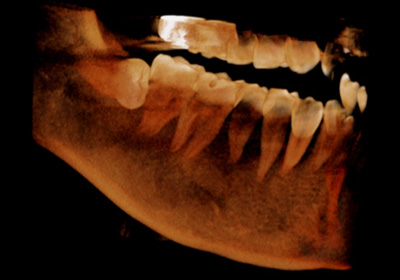

水平埋伏歯3D像